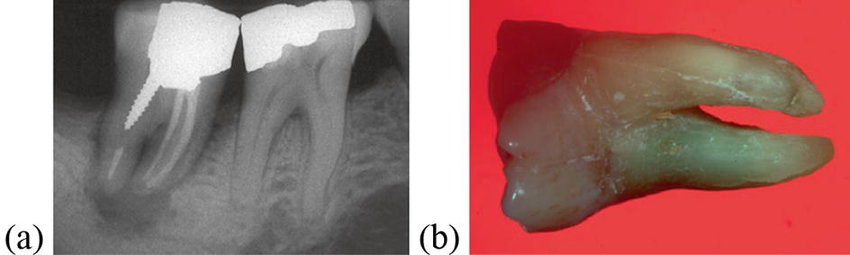

Tooth decay happens when starches and sugar feed on the teeth, attacking this. If you don’t handle this, it leads to fillings, crowns, extractions, and root canals, which are expensive and not fun.

Gum disease is another problem that happens whenever you don’t’ take care of your teeth. Because of the buildup of plaque and the tartar is left there untreated, it gets into the gums, making them swollen with a red color, and bleeding as well. This can get really bad, eventually ruining your gums, bones, and the tissue as well, and in severe gum disease cases, it results in tooth loss as well.